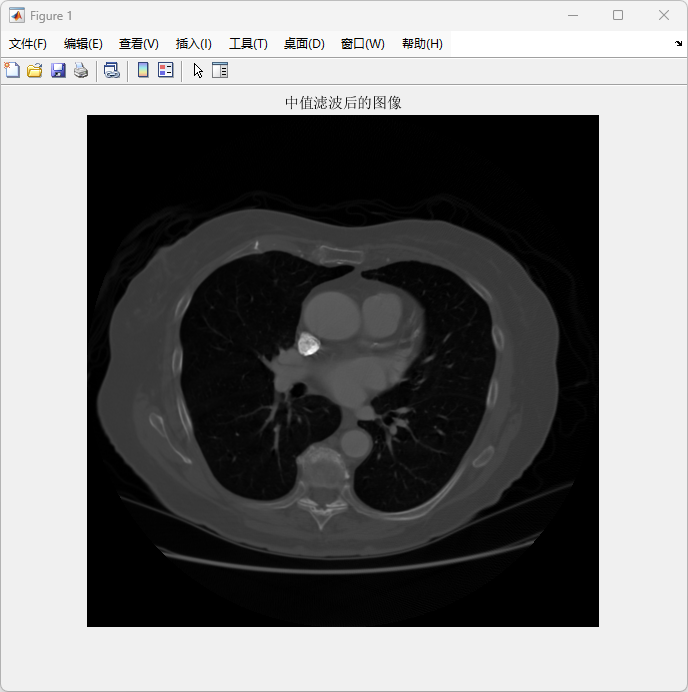

本研究提出了一种基于分水岭算法的肺结节检测与分析方法,以DICOM格式的医学影像为研究对象,结合多步骤图像处理技术,对影像中的目标区域(如肺结节)进行分割、检测和分析。首先,利用中值滤波对原始DICOM图像进行预处理,有效去除噪声,同时保留了重要的边缘信息,确保后续分割的精确性。在分割阶段,采用经典分水岭算法,并通过改进的分水岭方法优化了分割结果,避免了因过分割造成的区域碎片化问题。

运行 main.m

图像 1 – 原始图像

展示了未处理的DICOM图像,清晰显示了胸腔的结构。该图像为后续处理提供基础。